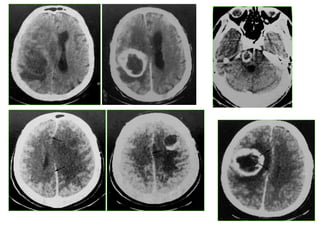

Hématome intra parenchymateux :

• C’est une collection hématique de siège intra

parenchymateux

• TDM : collection intra parenchymateuse

spontanément hyperdense entourée d’une

hypodensité correspondant à l’oedème cérébral

L’hématome évolue vers l’hypodensité voire la

liquéfaction

Calcifications possibles après plusieurs années

1- Hématome intra parenchymateux spontanément

hyperdense

2- Œdème hypodense

Hématome intra parenchymateux: • C’est une collection hématique de siège intra parenchymateux • Rx crane: – normale – syndrome d’HTIC • TDM : collection intra parenchymateuse spontanément hyperdense entourée d’une hypodensité correspondant à l’oedème cérébral L’hématome évolue vers l’hypodensité voire la liquéfaction Calcifications possibles après plusieurs années

1- Hématome intraparenchymateux spontanément hyperdense 2- Œdème hypodense 1 2